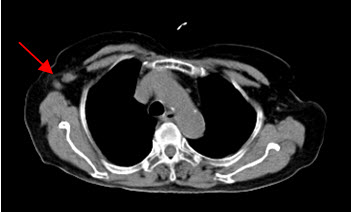

Hình 2a: Hình PET toàn thân của bệnh nhân Đỗ Thị N., 87 tuổi. thấy khối u ở vú phải (mũi tên đỏ) và hai hạch nách phải (mũi tên xanh) tăng hấp thu FDG.

Hình 2b: cho thấy rõ mức độ tập trung cao FDG tại vùng có khối u ở vú phải, max SUV=10,24.

Hình 2c: cho thấy hình ảnh hai hạch nách tăng hấp thu FDG (hạch di căn ung thư vú).

Nguồn: Mai Trọng Khoa – Trung tâm Y học hạt nhân và ung bướu – BV Bạch Mai)